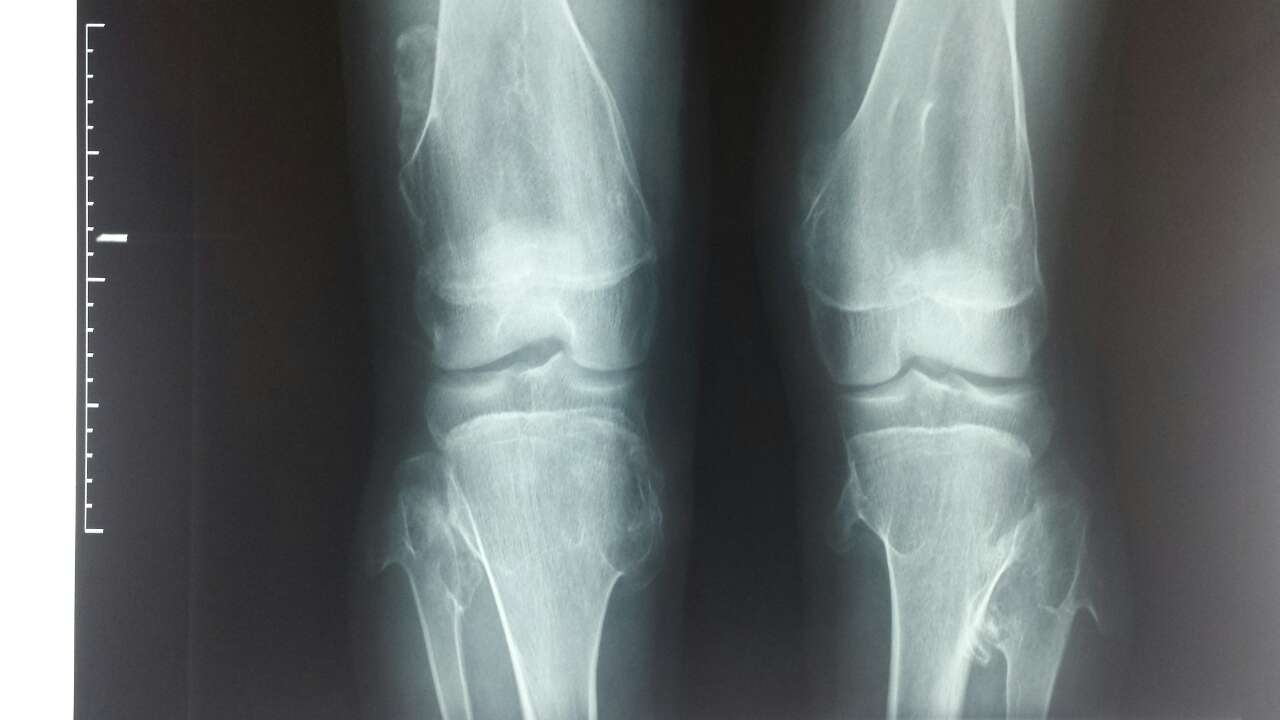

右胫骨上段骨软骨瘤

图片尺寸680x907